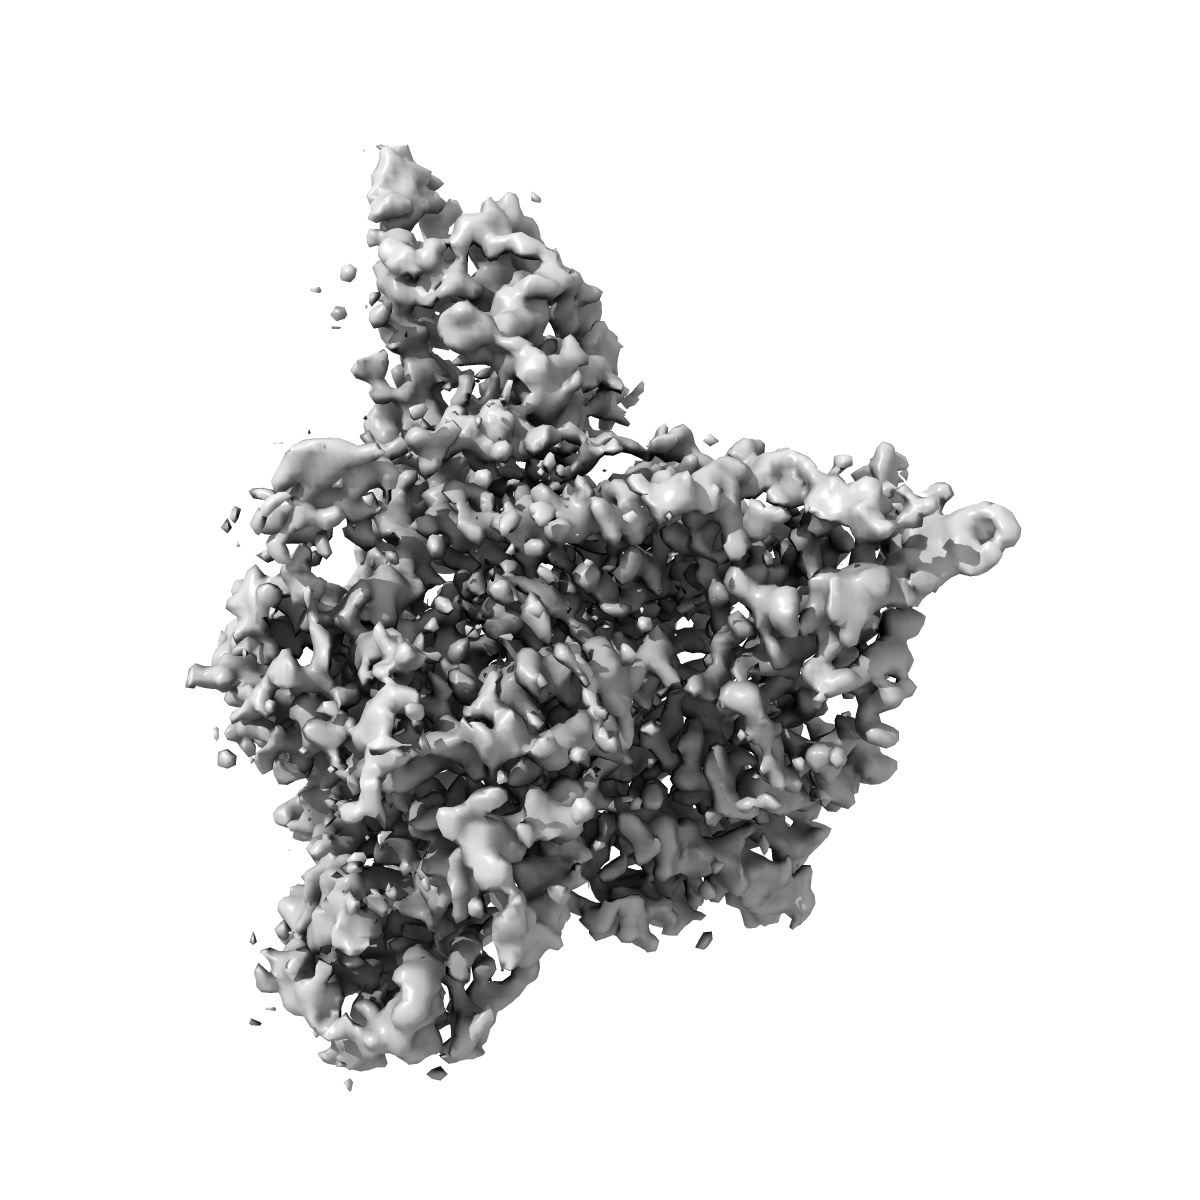

Cryo-EM structure of p110alpha in complex with p85alpha inhibited by BYL-719

Single-particle2.92 Å

Sample: Heterodimer of p110alpha with p85alpha

Cryo-EM structures of PI3K alpha reveal conformational changes during inhibition and activation.